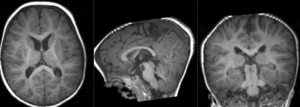

Registration Results

RegLib C49 unregistered.gif MR/CT before registration (click to enlarge)

RegLib C49 registered1 T2B0.gif alignment of T2 to B0 (click to enlarge)

RegLib C49 registered2 T1T2.gif preliminary affine alignment of T1 to T2 (click to enlarge)

RegLib C49 registered3 T1B0.gif final alignment of T1 to B0 (click to enlarge)